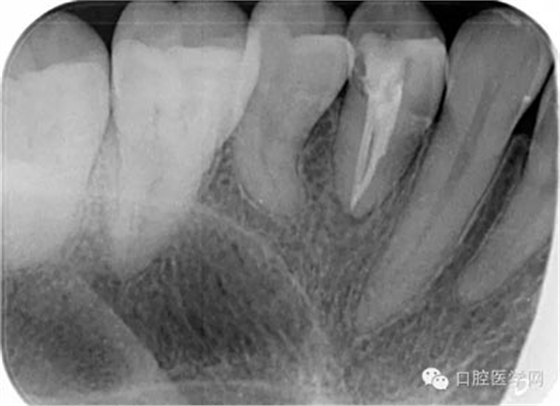

第六步:運用S3鑷鈦系統(tǒng)進行根管成形: 1S銼為04錐度20# 進入根管口后啟動馬達。沿根管走向上下提拉3,4次。到達根管長度后,退出根管,大量5.25%次氯酸鈉沖洗。根尖有碎屑堆積時,可用15#不銹鋼K銼疏通根管。

2S銼為06錐度25# 在系統(tǒng)銼中如感到阻力可運用輕微的力以“啄”的手法運動。每次前進1mm

直至工作長度。后退時以“刷”的手法進行運動。每次預備完成,就要用大量5.25%次錄酸鈉沖洗。

3S銼為04錐度35# 鑷鈦根管銼在根管內(nèi)預備時停留時間不超過5秒,每次都應該加入EDTA進行根管潤滑,并每次退出根管銼時,都應該用大量次氯酸鈉沖洗。

第七步:根管充填 使用對應錐度及號數(shù)的牙膠尖充填。